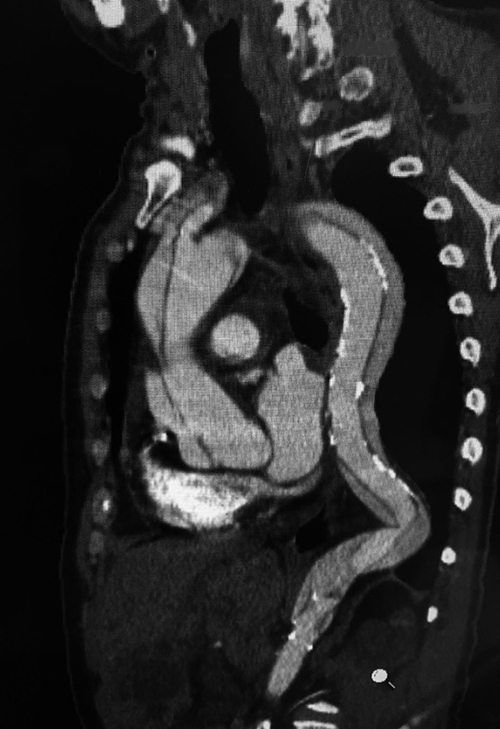

主要診斷要靠電腦斷層切片,如下圖就是一個主動脈內層多處破裂的案例。

(圖片來源:《俠醫楊智鈞的50道心臟密碼》)(圖片來源:《俠醫楊智鈞的50道心臟密碼》)